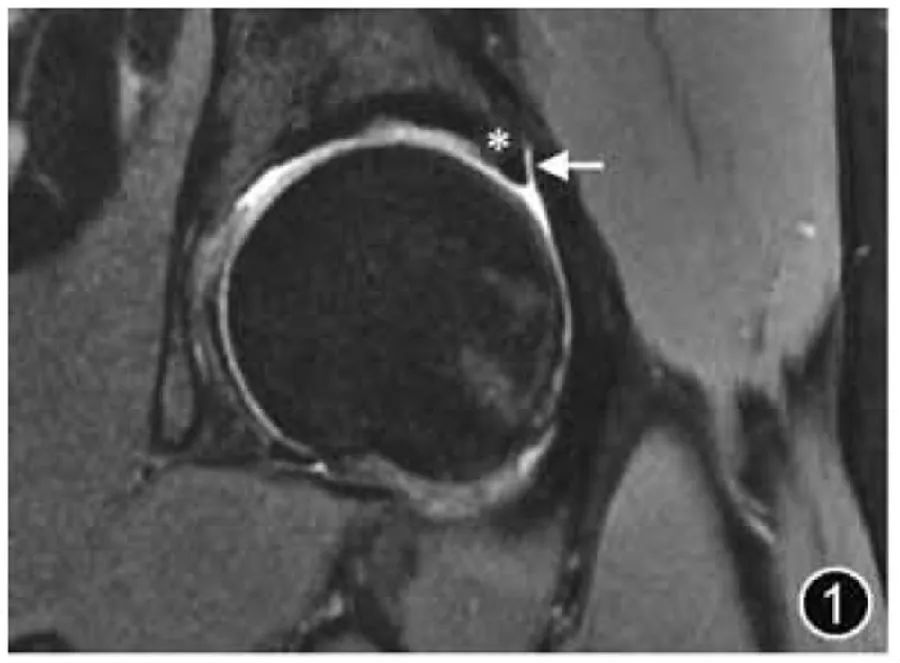

Тазобедренный сустав представляет собой шаровидный сустав, состоящий из головки бедренной кости и вертлужной впадины. За исключением центральной ямки, головка бедренной кости покрыта гиалиновым хрящом и доходит до места соединения головки и шейки бедренной кости. Суставная поверхность вертлужной впадины имеет серповидную форму, а суставной хрящ покрывает ее переднюю, верхнюю и заднюю области. Таз и проксимальный отдел бедренной кости являются резервными участками для красного костного мозга, поэтому сигнал костного мозга в тазу и проксимальном отделе бедренной кости обычно присутствует. неравномерно (рис. 1).

Рисунок 1. МРТ-изображение нормальной вертлужной губы. Корональная Т2-ВИ четко показывает капсулу сустава (↑) и переход губного хряща (*).